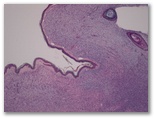

1332-R3-Neurofibroma

1. Neurofibroma